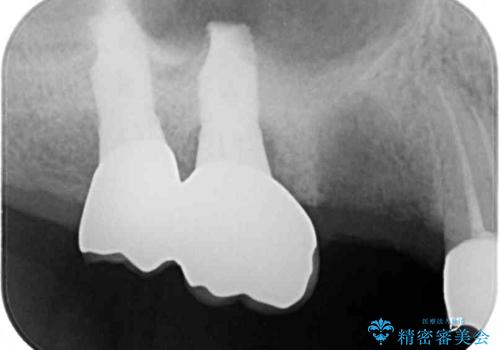

- 咬合力により歯が割れてしまった方のインプラント治療です。

抜歯後4ヶ月ほど待ち、後方のインプラントと同一メーカーのインプラントを埋入することとしました。